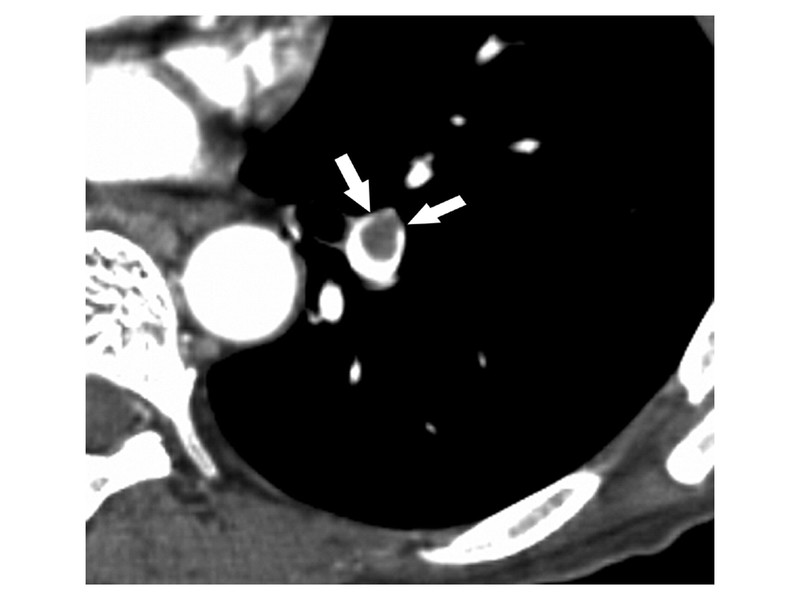

MDCT: Nearly 1 in 4 respondents suggested computed tomographic pulmonary angiography (CTPA) as the main diagnostic test.

Nowadays, CTPA has become the imaging procedure of choice in patients with suspected PE. Compared with V/Q scans, CTPA has several advantages:

- ▲ diagnostic accuracy

- Ability to provide a clear test result (either +ve or –ve i.e. rule in or rule out PE)

- Faster acquisition time with high-contrast images

- ▲ availability

- Can suggest alternate diagnosis as well, such as pneumonia, ARDS, COAD, structural defects in the heart and lungs etc.

PIOPED II investigators reported MD-CTPA to have a sensitivity of 83% and a specificity of 96% for diagnosing PE. In clinical practice, if the clinical suspicion is moderate to high (as in our case), CTPA is an appropriate initial diagnostic method.

CT scan demonstrates a pulmonary embolus that results in an eccentrically positioned partial filling defect, which is surrounded by contrast material and forms acute angles with the arterial wall (arrows).